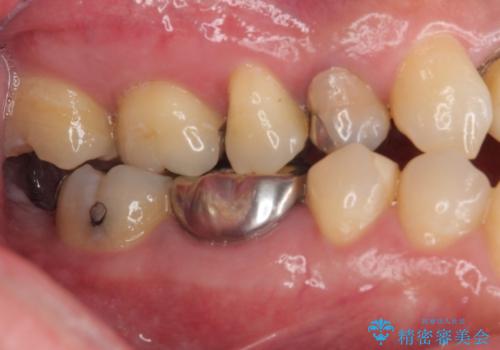

- 適合の良くない銀の詰め物が入っており、白い詰め物へのやり替えをご希望された患者様です。

メタルインレーを除去したところ、虫歯ができていたため取り除いたうえでハイブリッドインレー修復を行いました。

インレーセット時には唾液の侵入を防ぐためにラバーダム防湿を行っています。

Ⅲ級咬合の患者さまで、奥歯への負荷が強いため、セラミックよりも破損のリスクが低いハイブリッドインレー治療を行いました。